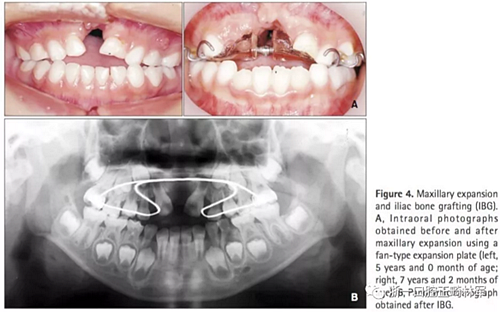

第一階段(圖4及表2)

上頜牙弓使用fan-type擴弓器(慢擴,0.25mm/周)。7歲7月時行IBG,隨后上頜恒側切牙與移植區(qū)萌出。